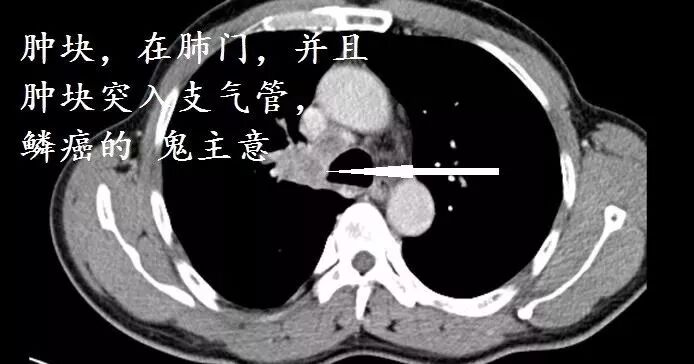

肺门肿块,肿块侵入支气管,鳞癌。假如出现阻塞性肺炎,更支持鳞癌

这个病例,肿块与支气管的走形大约平行,小细胞肺癌可能性很大。

这个病例,小细胞肺癌。

为什么?因为小细胞肺癌忙着拼命生长,远处转移,一般没有时间阻塞支气管。鳞癌则容易阻塞支气管,小细胞肺癌则喜欢到处跑,不喜欢阻塞支气管让你断气,而是从远处攻击你。